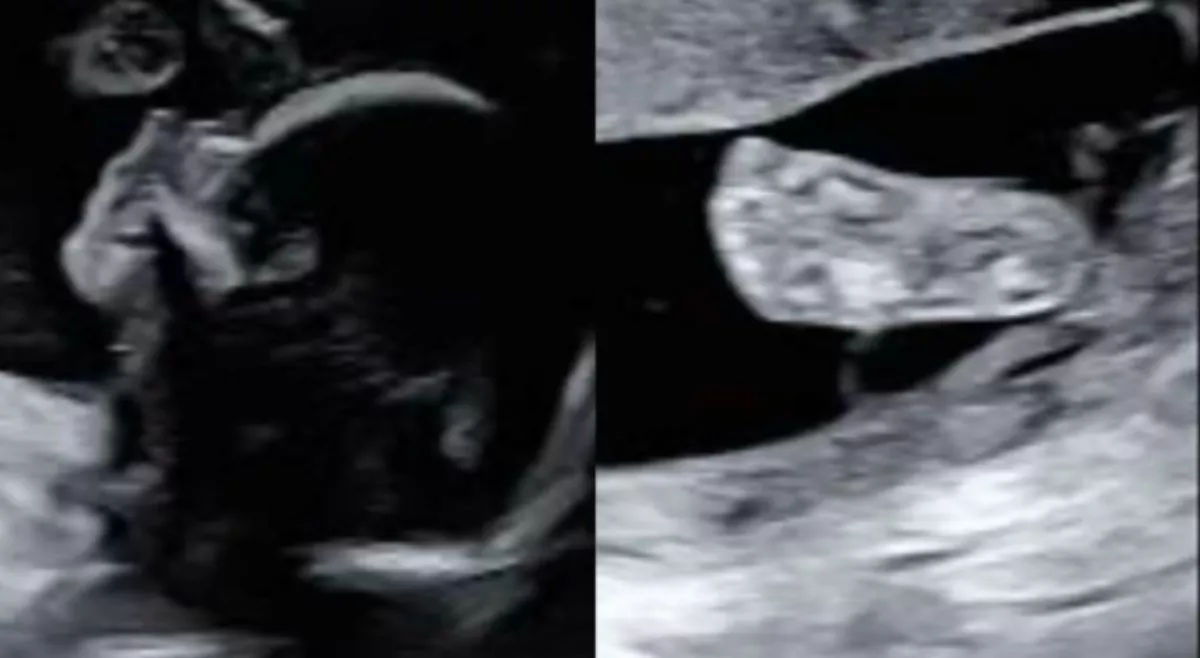

A terhesség alatti ultrahangvizsgálatok vad érzelmek keverékét jelentik a szülők számára: egyrészt izgatottak, hogy megpillanthatják gyermeküket, másrészt attól tartanak, hogy valami rendellenességet fedez fel az orvos. Ez a 27 éves nő saját maga vette észre valamit - a látvány furcsán ismerősnek tűnt számára...

A skót Inês Egner a terhesség 20. hetében volt, amikor a méhében lévő baba fontos vizsgálatát tervezték. "Nagyon izgatottak voltunk a szervszűrés miatt" - írta a skót nő a TikTokon. A 27 éves a nő férjével és legjobb barátjával együtt ment az orvoshoz, ahol részletesen megvizsgálták a magzat szerveinek fejlődését. Utána mindhármuknak a váróteremben kellett várniuk, amíg a nőgyógyász átadta nekik a vizsgálati eredményeket és az ultrahangképeket.

„Hárman együtt néztük az ultrahangképet, ahogy az ember szokta, csodálva az apró kezeket és az orrot”

– emlékezett vissza Inês a People magazinnak.